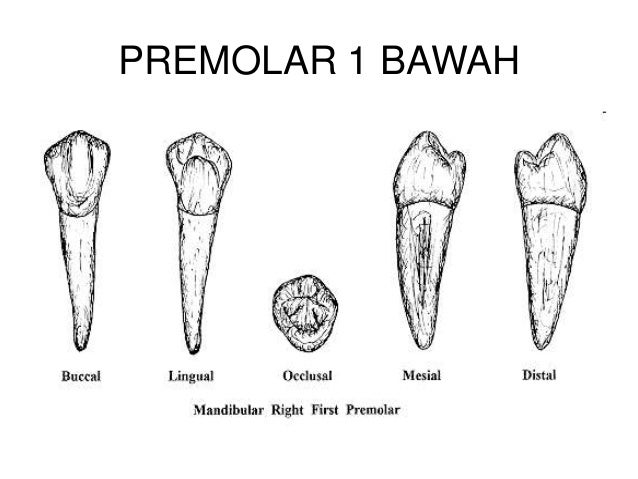

2. dental anatomi gigi permanen ..

2. dental anatomi gigi permanen ..

2. dental anatomi gigi permanen ..

2. dental anatomi gigi permanen ..

10. morfologi gigi permanent rahang bawah

10. morfologi gigi permanent rahang bawah

Anatomi Gigi Premolar

Anatomi Gigi Premolar

klasifikasi gigi molar dan premolar pada dental